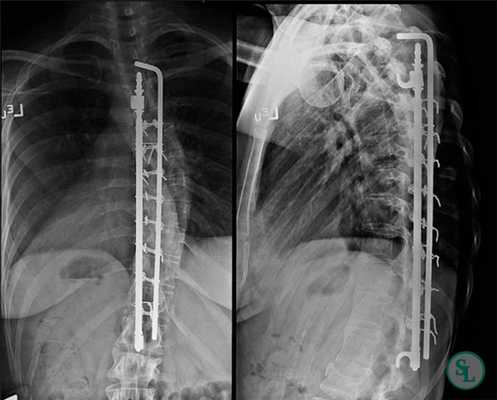

Клинический пример: больная Н., 1999 г.р., прооперированная по поводу сколиотической болезни (рис.1-4):

Рис.4. Передняя и боковая спондилограмма после операции